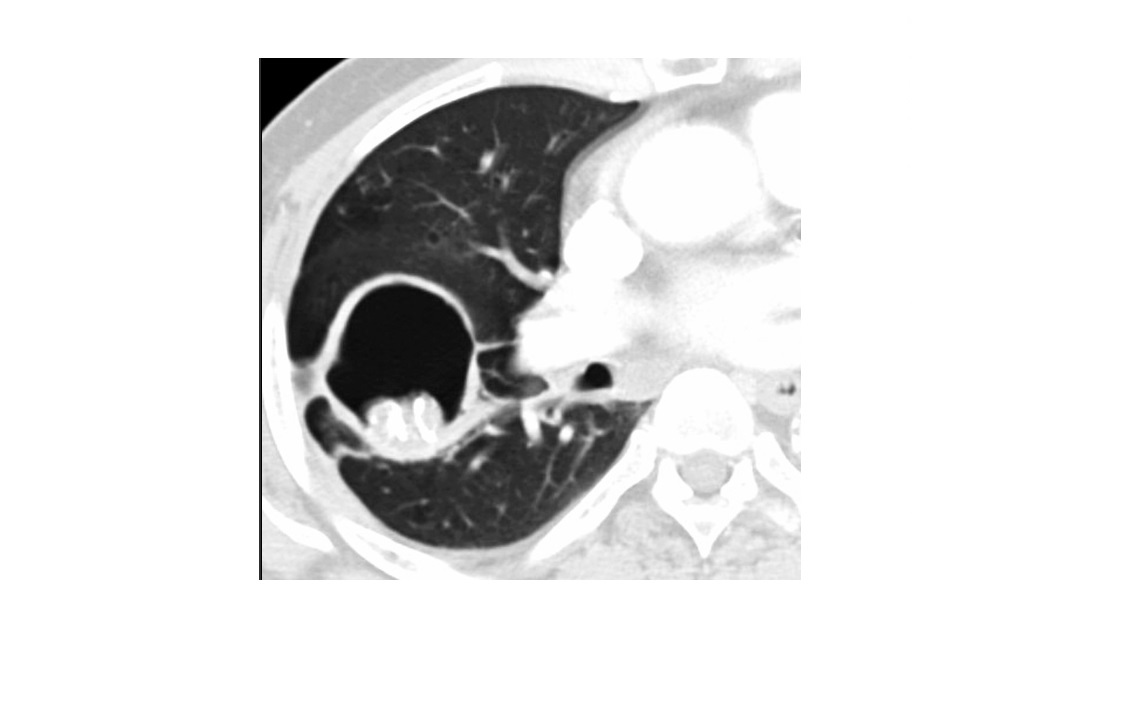

DIP

Bilateral, lower zone predominant ground-glass opacities

± subpleural **intralobular lines/retiuclations **

Small, round,** thin-walled** (2-4 mm in diameter)